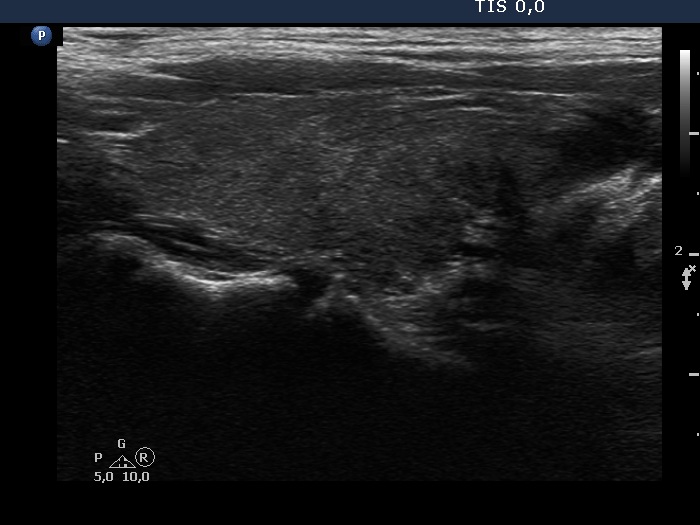

Parathyroid lesions - case 148 (ultrasonographic picture 3)

Right lobe, longitudinal view.